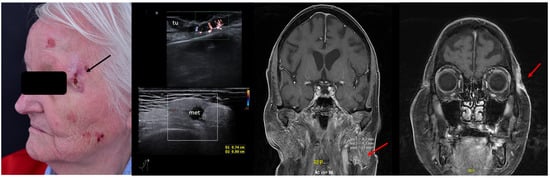

2. Enhancement of Diagnostic Accuracy, Avoidance of Misdiagnosis, Early Identification of Local Relapse

7. Choice of Surgical Approach

8. Preoperative Neuro-Vascular Mapping